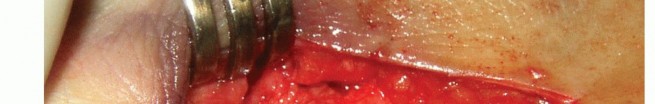

A dorsal 3-cm longitudinal incision is made over the second MTP joint, the extensor tendons are retracted, and the capsule is incised to expose the MTP joint.

Collaterals are then released to facilitate delivery of the second metatarsal head dorsally out of the wound.

Plantarflexion at the MTP allows for optimal exposure of the articular surface of the second metatarsal.

With use of an oscillating saw, a cut is initiated at the articular surface of the most dorsal aspect of the

second metatarsal head.

The cut is carried proximally and parallel to the plantar plane of the foot (TECH FIG 6A).

The plantar osteotomy fragment is then grasped with a pointed reduction clamp and slid proximally to achieve the desired amount of shortening (TECH FIG 6B).

The osteotomy is finally secured with a compression screw placed in lag fashion from dorsal to plantar (TECH FIG 6C).

The excess dorsal bony prominence is shaved to a smooth surface.